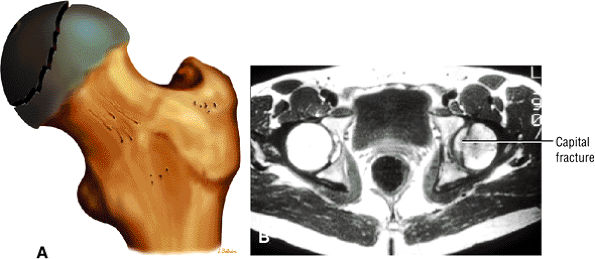

Characterized by posterior inferior displacement of the proximal femoral epiphysis

MR demonstrates a widened growth plate and epiphyseal slippage.

Arthroscopy is used to evaluate articular cartilage and labral injury and to decompress hematoma caused by physeal fracture.